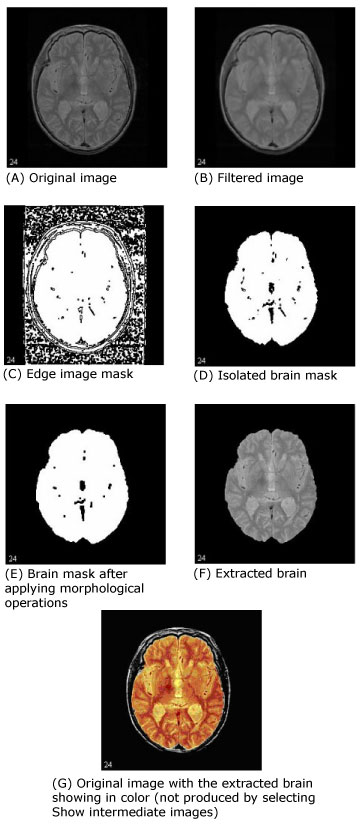

The first step that MIPAV performs is to filter the original image to remove irregularities, thus making the next step-edge detection-easier. The filter chosen for this was the Filters (Spatial): Regularized Isotropic (Nonlinear) Diffusion. Figure 1-A shows the original image, and Figure 1-B shows the image after it is filtered.

Next, MIPAV performs a thresholded zero-crossing detection of the filtered image's laplacian. This process marks positive areas of the laplacian image as objects by setting them to 1 and identifies nonobject areas by setting their values to 0 (Figure 1-C).

During this step, the software performs a number of 3D (or, optionally, 2.5D) morphological erosions on the edge image mask to remove small areas identified as objects that are not a part of the brain. It then performs a search for the largest 3D region within the image, which should be the brain (Figure 1-D). It erases everything outside this region and then performs another morphological operation, dilating the brain image back to approximately its original size and shape before the erosion (Figure 1-E).

As an option, MIPAV can then fill in any holes that still exist within the brain mask. Finally, it uses the mask to extract the brain image data from the original volume (Figure1-F).

Figure 1 shows images that were produced from running this algorithm with the default parameters against a 256 x 256 x 47 MRI. In each image, the middle slice is shown.

Figure 1. Examples of Extract Brain Surface (BSE) image processing